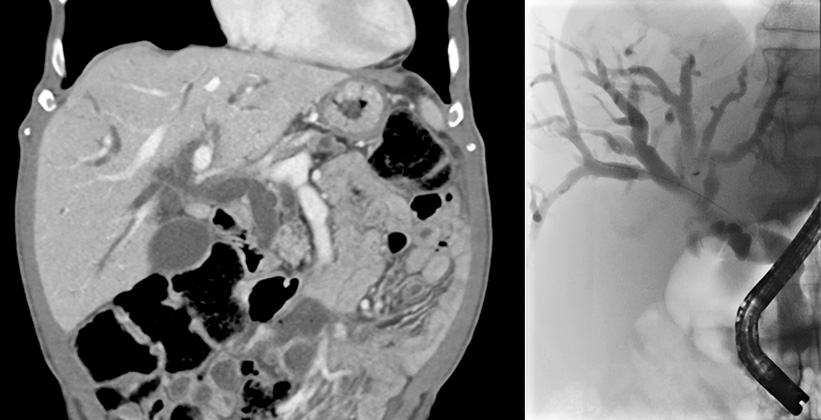

Datortomografi (t v) respektive endoskopisk retrograd kolangiopankreatografi (t h)av patient med tumör i papillområdet. Vida gallvägar observeras på båda bilderna.